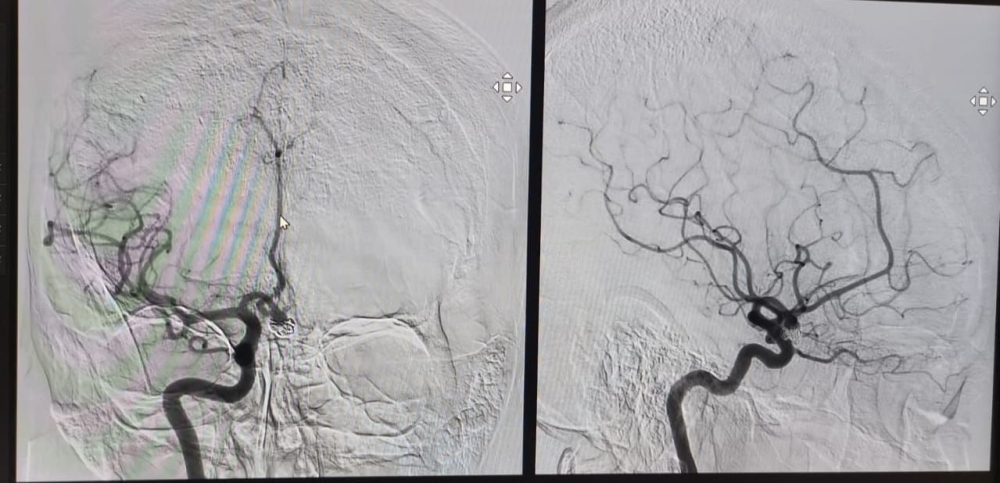

وتتضمن عملية استئصال الجلطات إدخال قسطرة شريانية عن طريق أحد الأوعية الدموية الموجودة في الفخذ، ومن ثمَّ الوصول إلى الشريان المُصاب في الدماغ لإزالة الجلطة باستخدام أجهزة متقدمة متخصصة لإزالة الجلطات، حيث تُجرى تلك العملية تحت تأثير التخدير العام أو الموضعي بحسب حالة المريض.